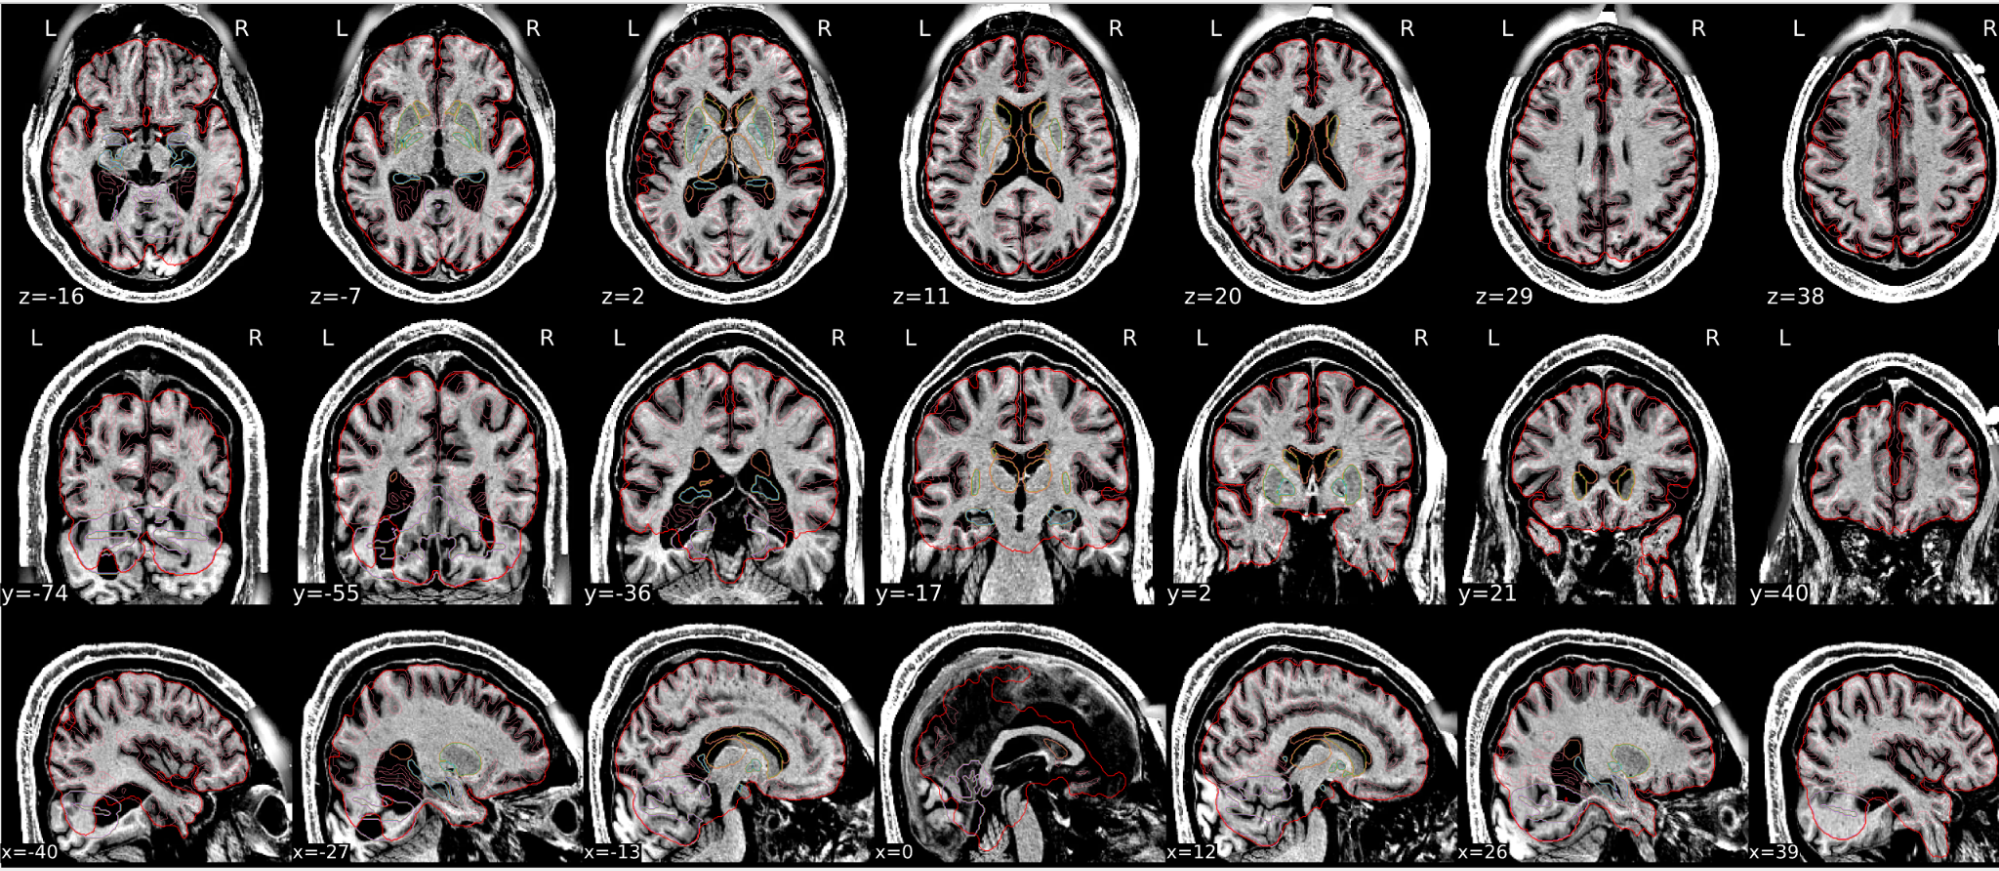

T1w skull stripping

Skull stripping is the process separating the brain (cortex and cerebellum) from the skull. The red line follows the outline of the brain and it separates it from the skull.

Example of a good subject

- There are no skull stripping errors, such as portions of the brain missing, or too much of the skull retained

- The red line follows the outline of the brain

Example of a bad subject

- There are skull stripping errors, such as portions of the brain missing, or too much of the skull retained

- NOTE: check all the images (slices) in the report. If only one image (slice) looks problematic, it is possible that the subject is okay and it is just a visual issue in that particular screenshot

Summary

| Good | Bad |

|---|---|

| The brain is fully inside the red line | Structures like the cranium or the eyes are inside the red line |

| No important brain structures are outside of the red line red line follows the natural outline of the brain | Important brain structures are missing inside of the red line |

-> if only one slice is problematic, it could be an issue related to the visual depiction of the data instead of an issue related to the test subject